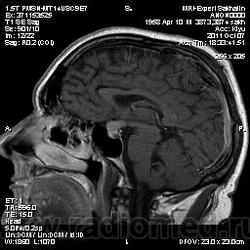

Аденома гипофиза

Вот такая аденома гипофиза сегодня.Мужчина с жалобами на снижение зрения.

Публикации: 175

Мне кажется что это все же не аденома, может глиома хиазмы ? (воронки гипофиза)? Или еще какое-нибудь объемное образование.... Что то меня смущает, еще не поняла что, но В любом случае наверное я бы однозначно не писала что это аденома, а выставила бы весь диф. ряд.

Танюша, обычно пишем "образование хиазмально-селлярной области"

Присоединяюсь к последнему коментарию, все таки откуда растет по моему мнению трудно однозначно сказать, лучше себя обезопасить написав "объемное образование хиазмально-селлярной области"